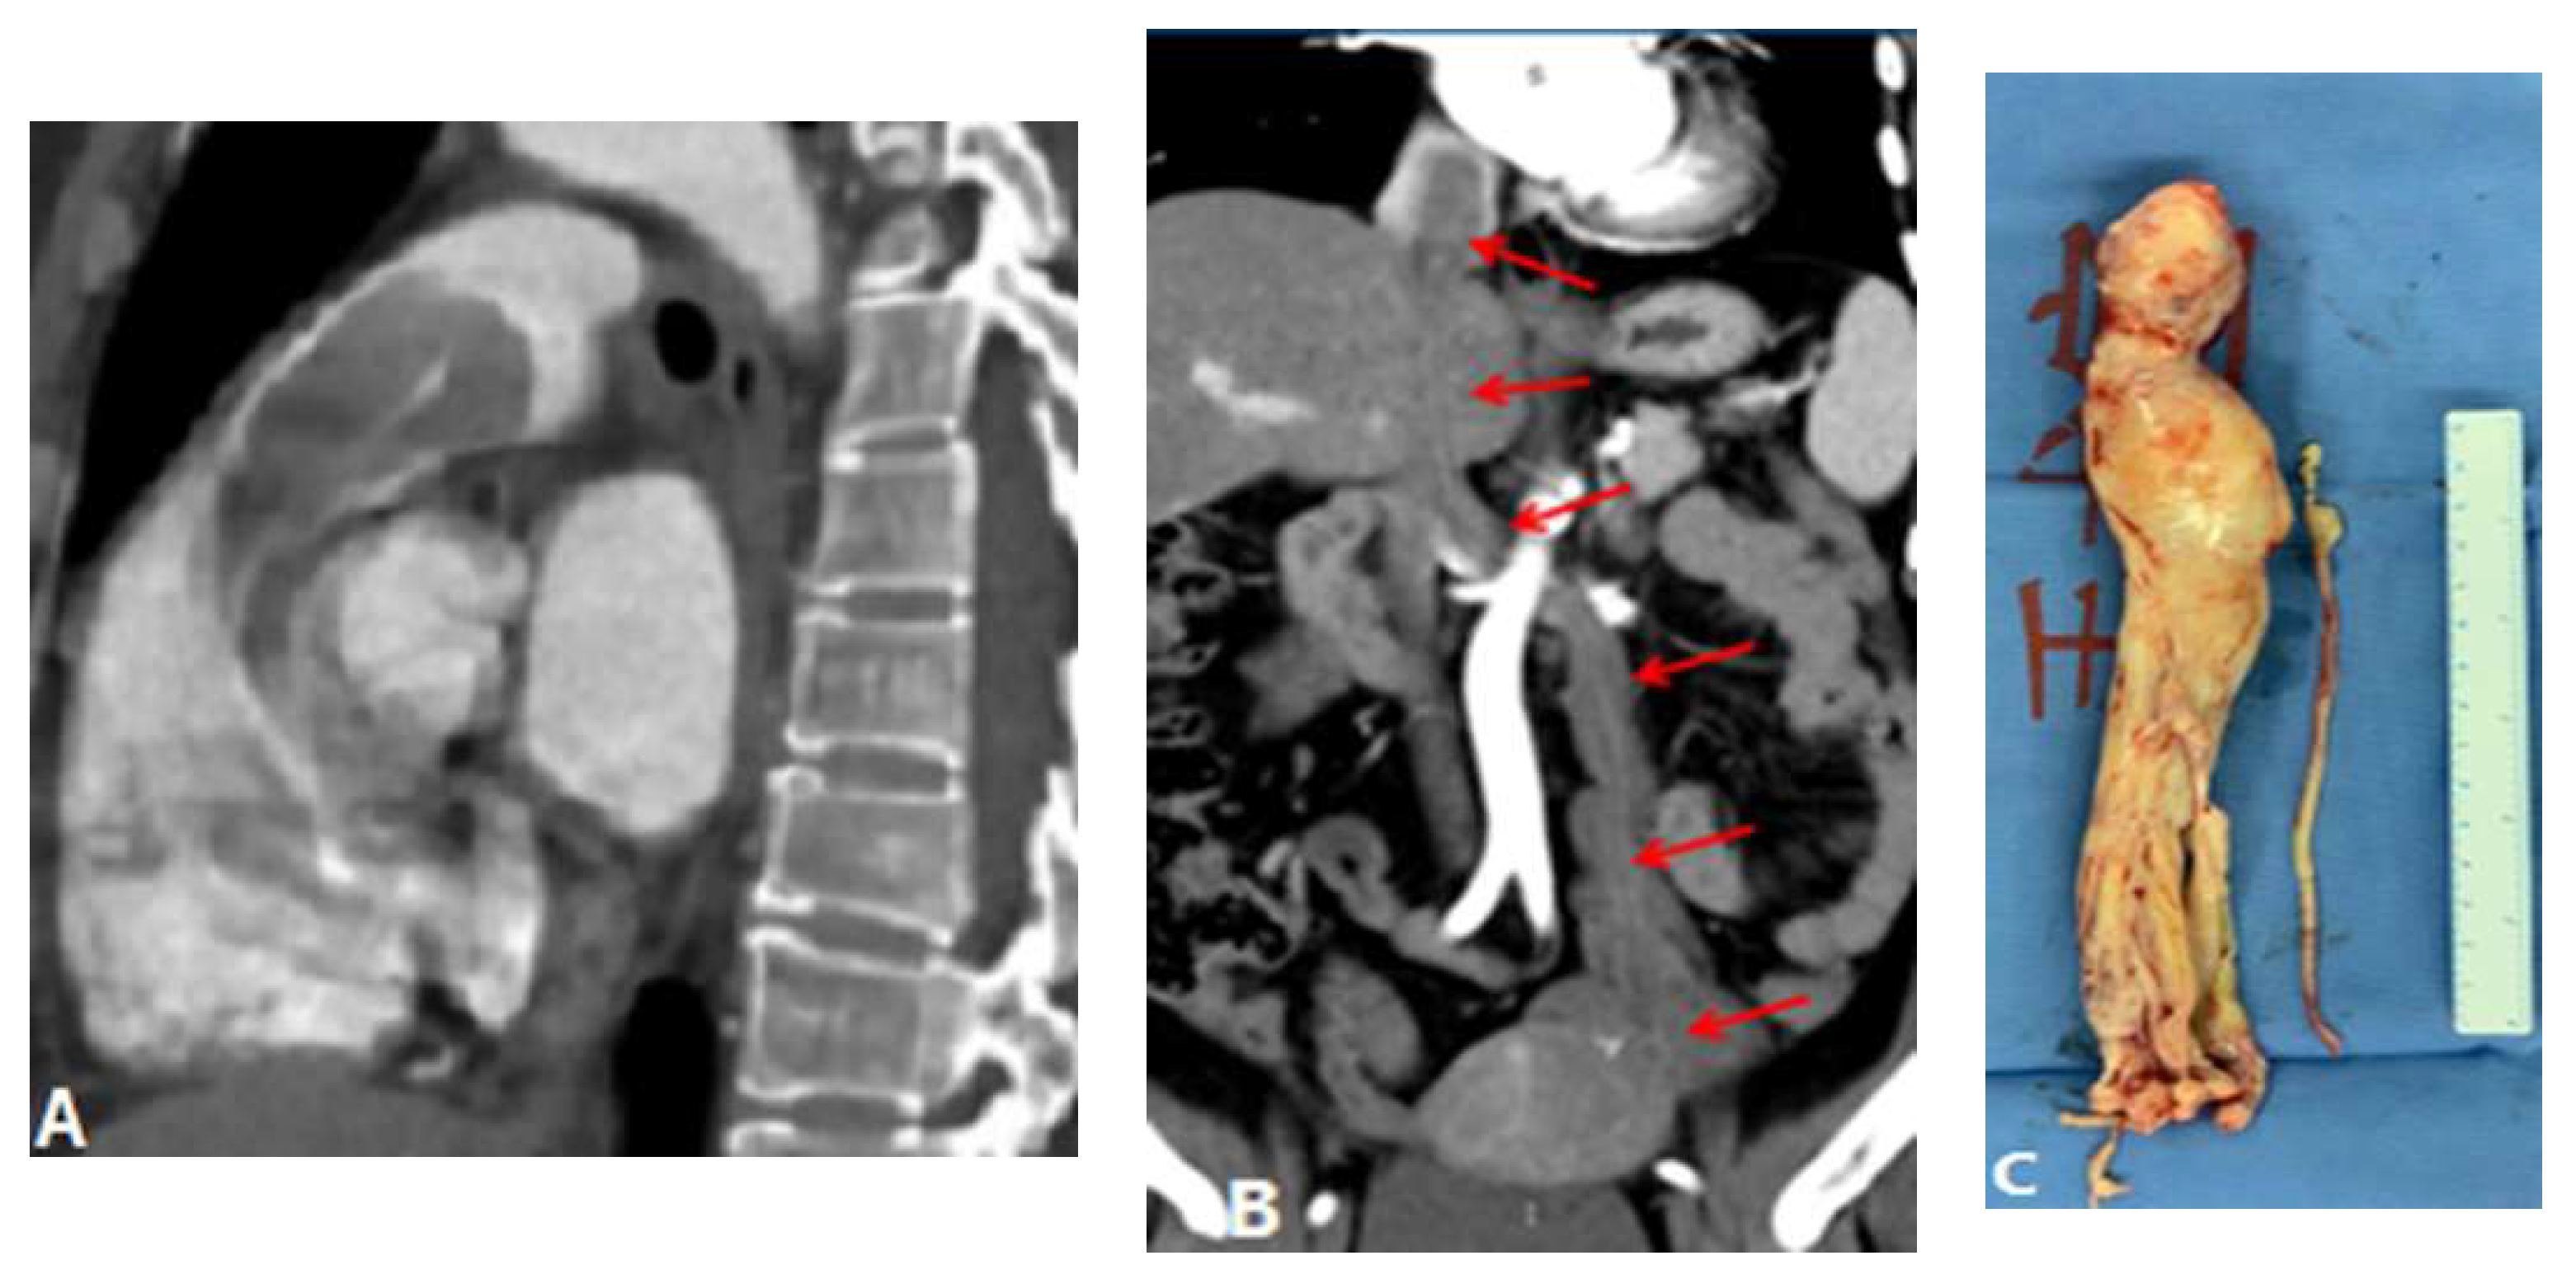

3.3.3. Aortic Aneurysm

4. Complications of Radiofrequency Ablation Of Atrial Fibrillation